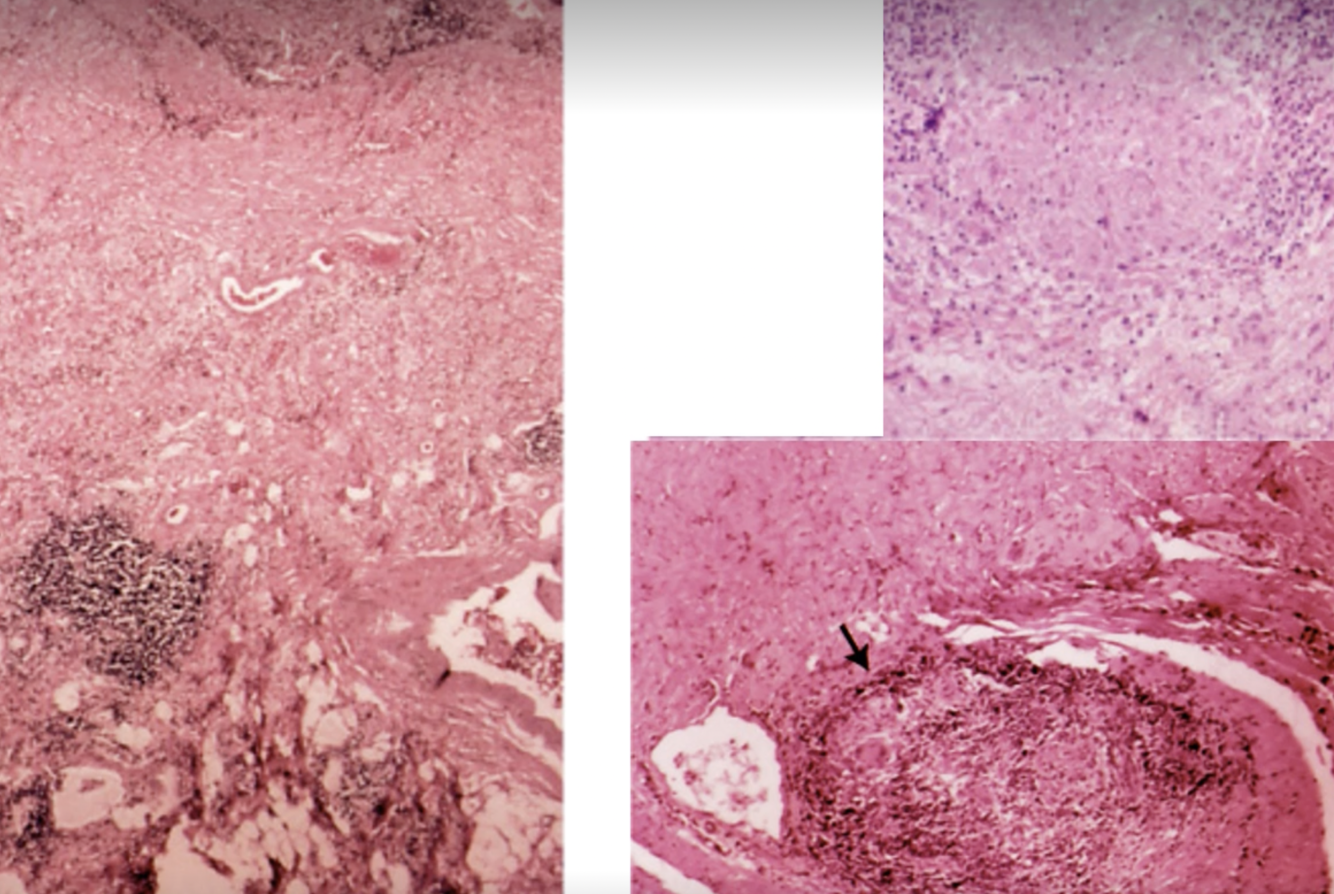

Hur ser crohns ut mikroskopiskt?

Transmural inflammation med möjlig

På bilden kan vi se granulom